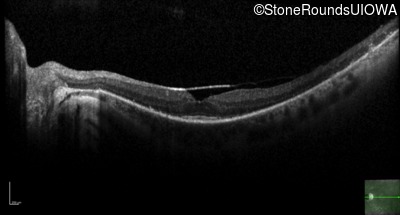

Optical Coherence Tomography - Left - 20/25 sc

Exemplar / OCT Stack

OCT Stack